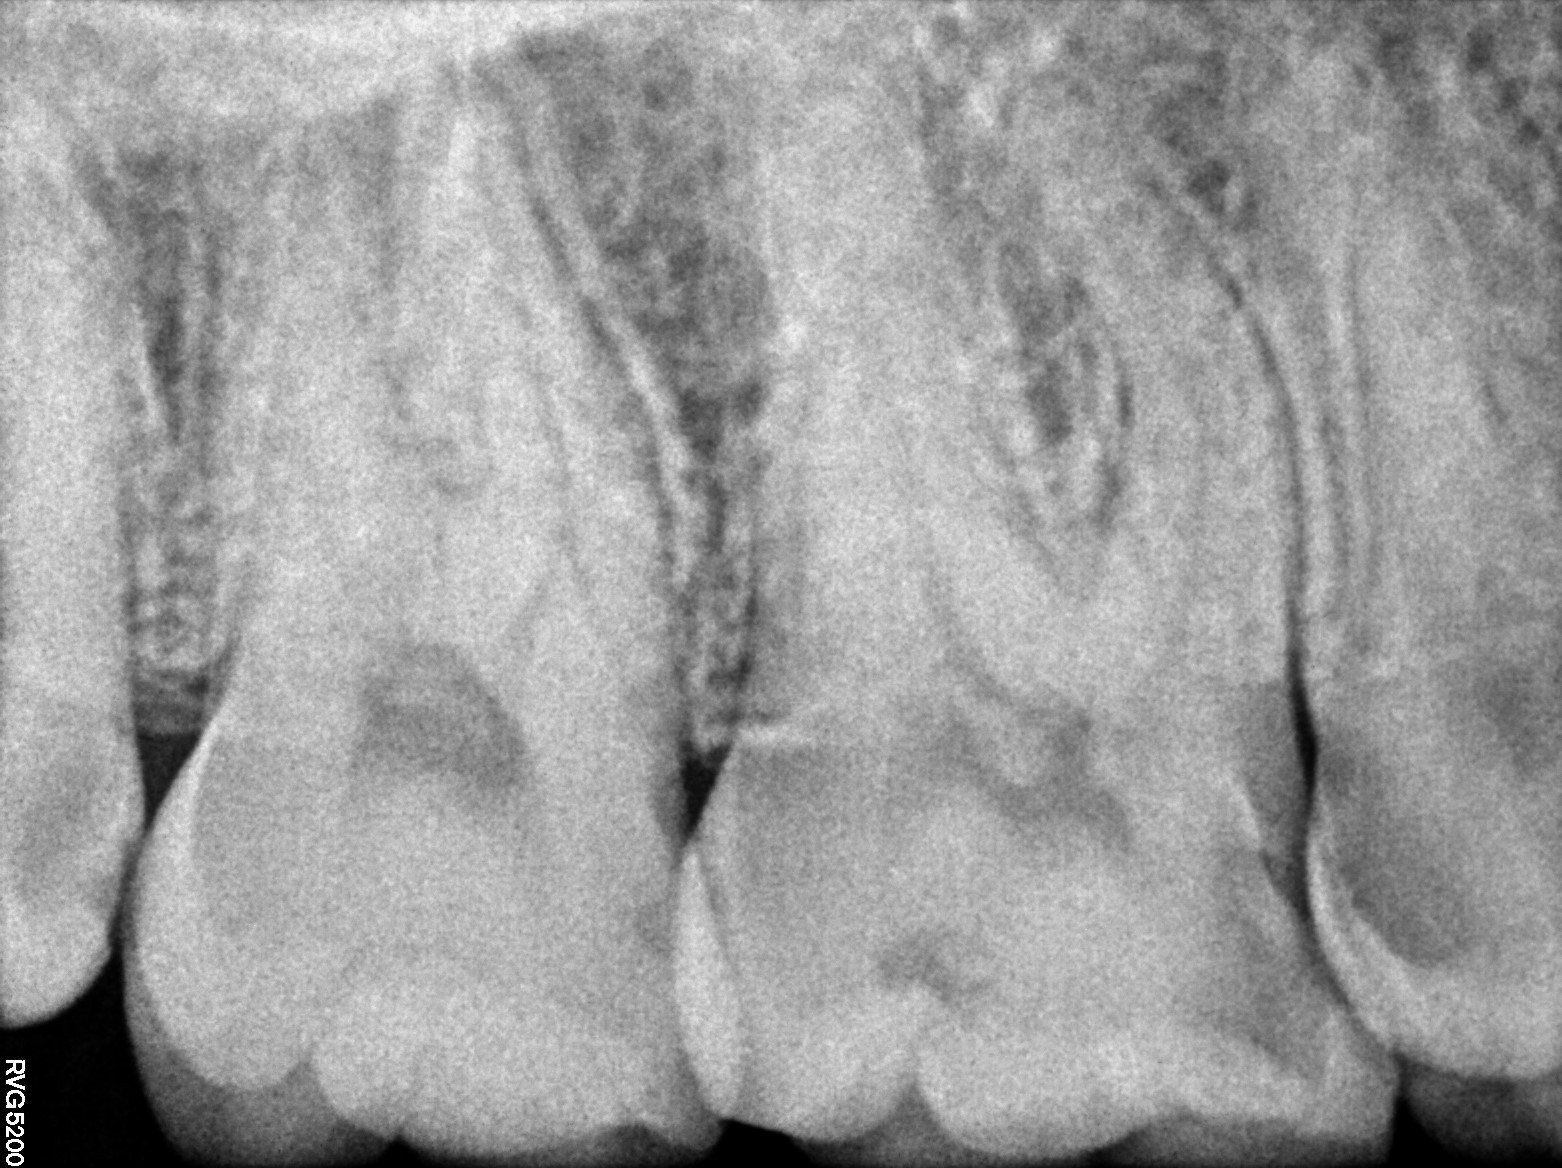

Dental Radiographs FHIR: DocumentReference · LOINC 24641-7

xray_1772642539_0.jpg

24641-7